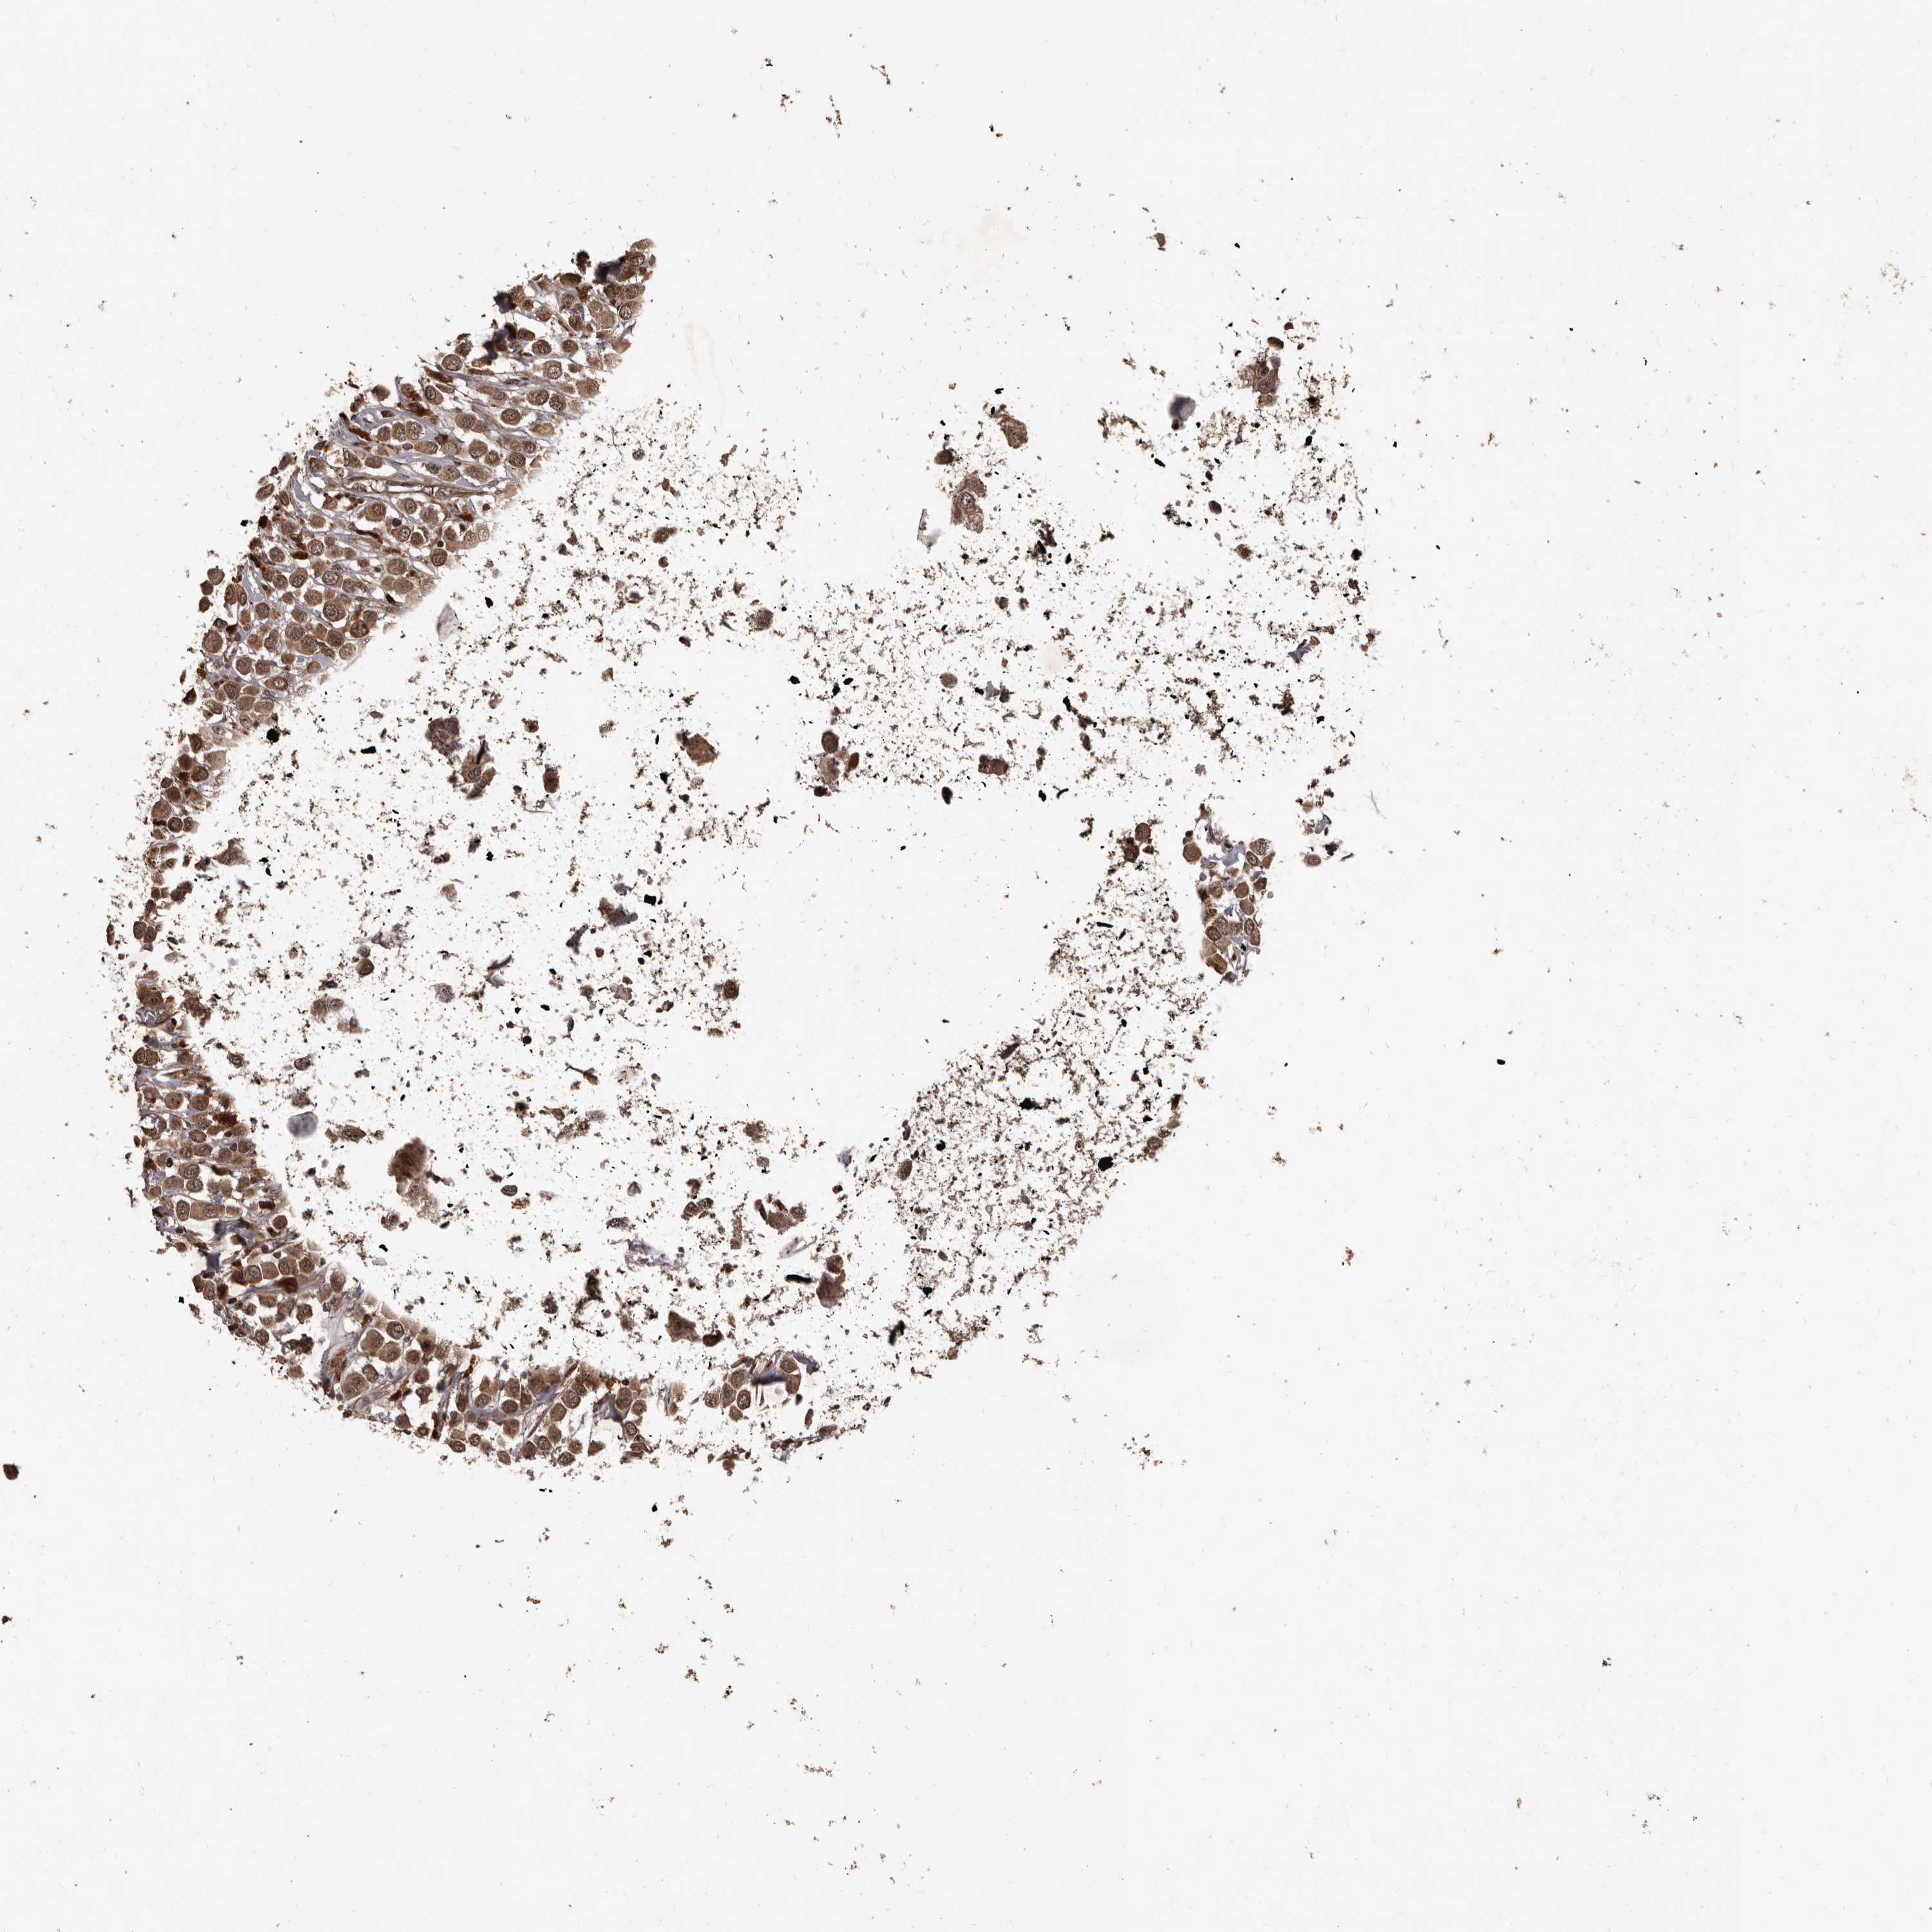

BRCA TCGA BRCA VALIDATION PROTEIN EXPRESSION